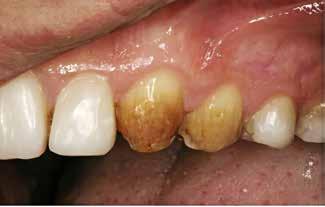

Klinisk undersøgelse viste emaljehypoplasier og hypomineralisering på 1+, +1, 2-, 1-, -1 og -2 (Fig.1). Hun havde Angle klasse II, pladsmangel i begge kæber og agenesi af -5. Der var isninger ved spisning og tandbørstning. Fundene var forenelige

BAGGRUND – Denne kasuistik beskriver en patient, hvor der blev valgt protetisk behandling i ung alder.

PATIENTTILFÆLDE – En niårig pige havde stort behandlingsbehov og smerter fra tænderne på grund af tandudviklingsforstyrrelse. Der var flere gange forsøgt restaurering med komposit, som ikke fungerede. Laminater i feldspatkeram blev valgt for at fjerne mindst mulig tandsubstans, øge holdbarheden på restaureringerne og forbedre æstetikken. Patientens motivation, meninger og kooperationsevne var vigtige for behandlingsvalget, da behandlingen var tidkrævende og til tider udmattende for en ung patient.

KONKLUSION – Resultatet var vellykket og medførte forbedret livskvalitet. Protetisk behandling med adhæsiv teknik kan være et godt behandlingsalternativ for børn og unge på ret indikation.